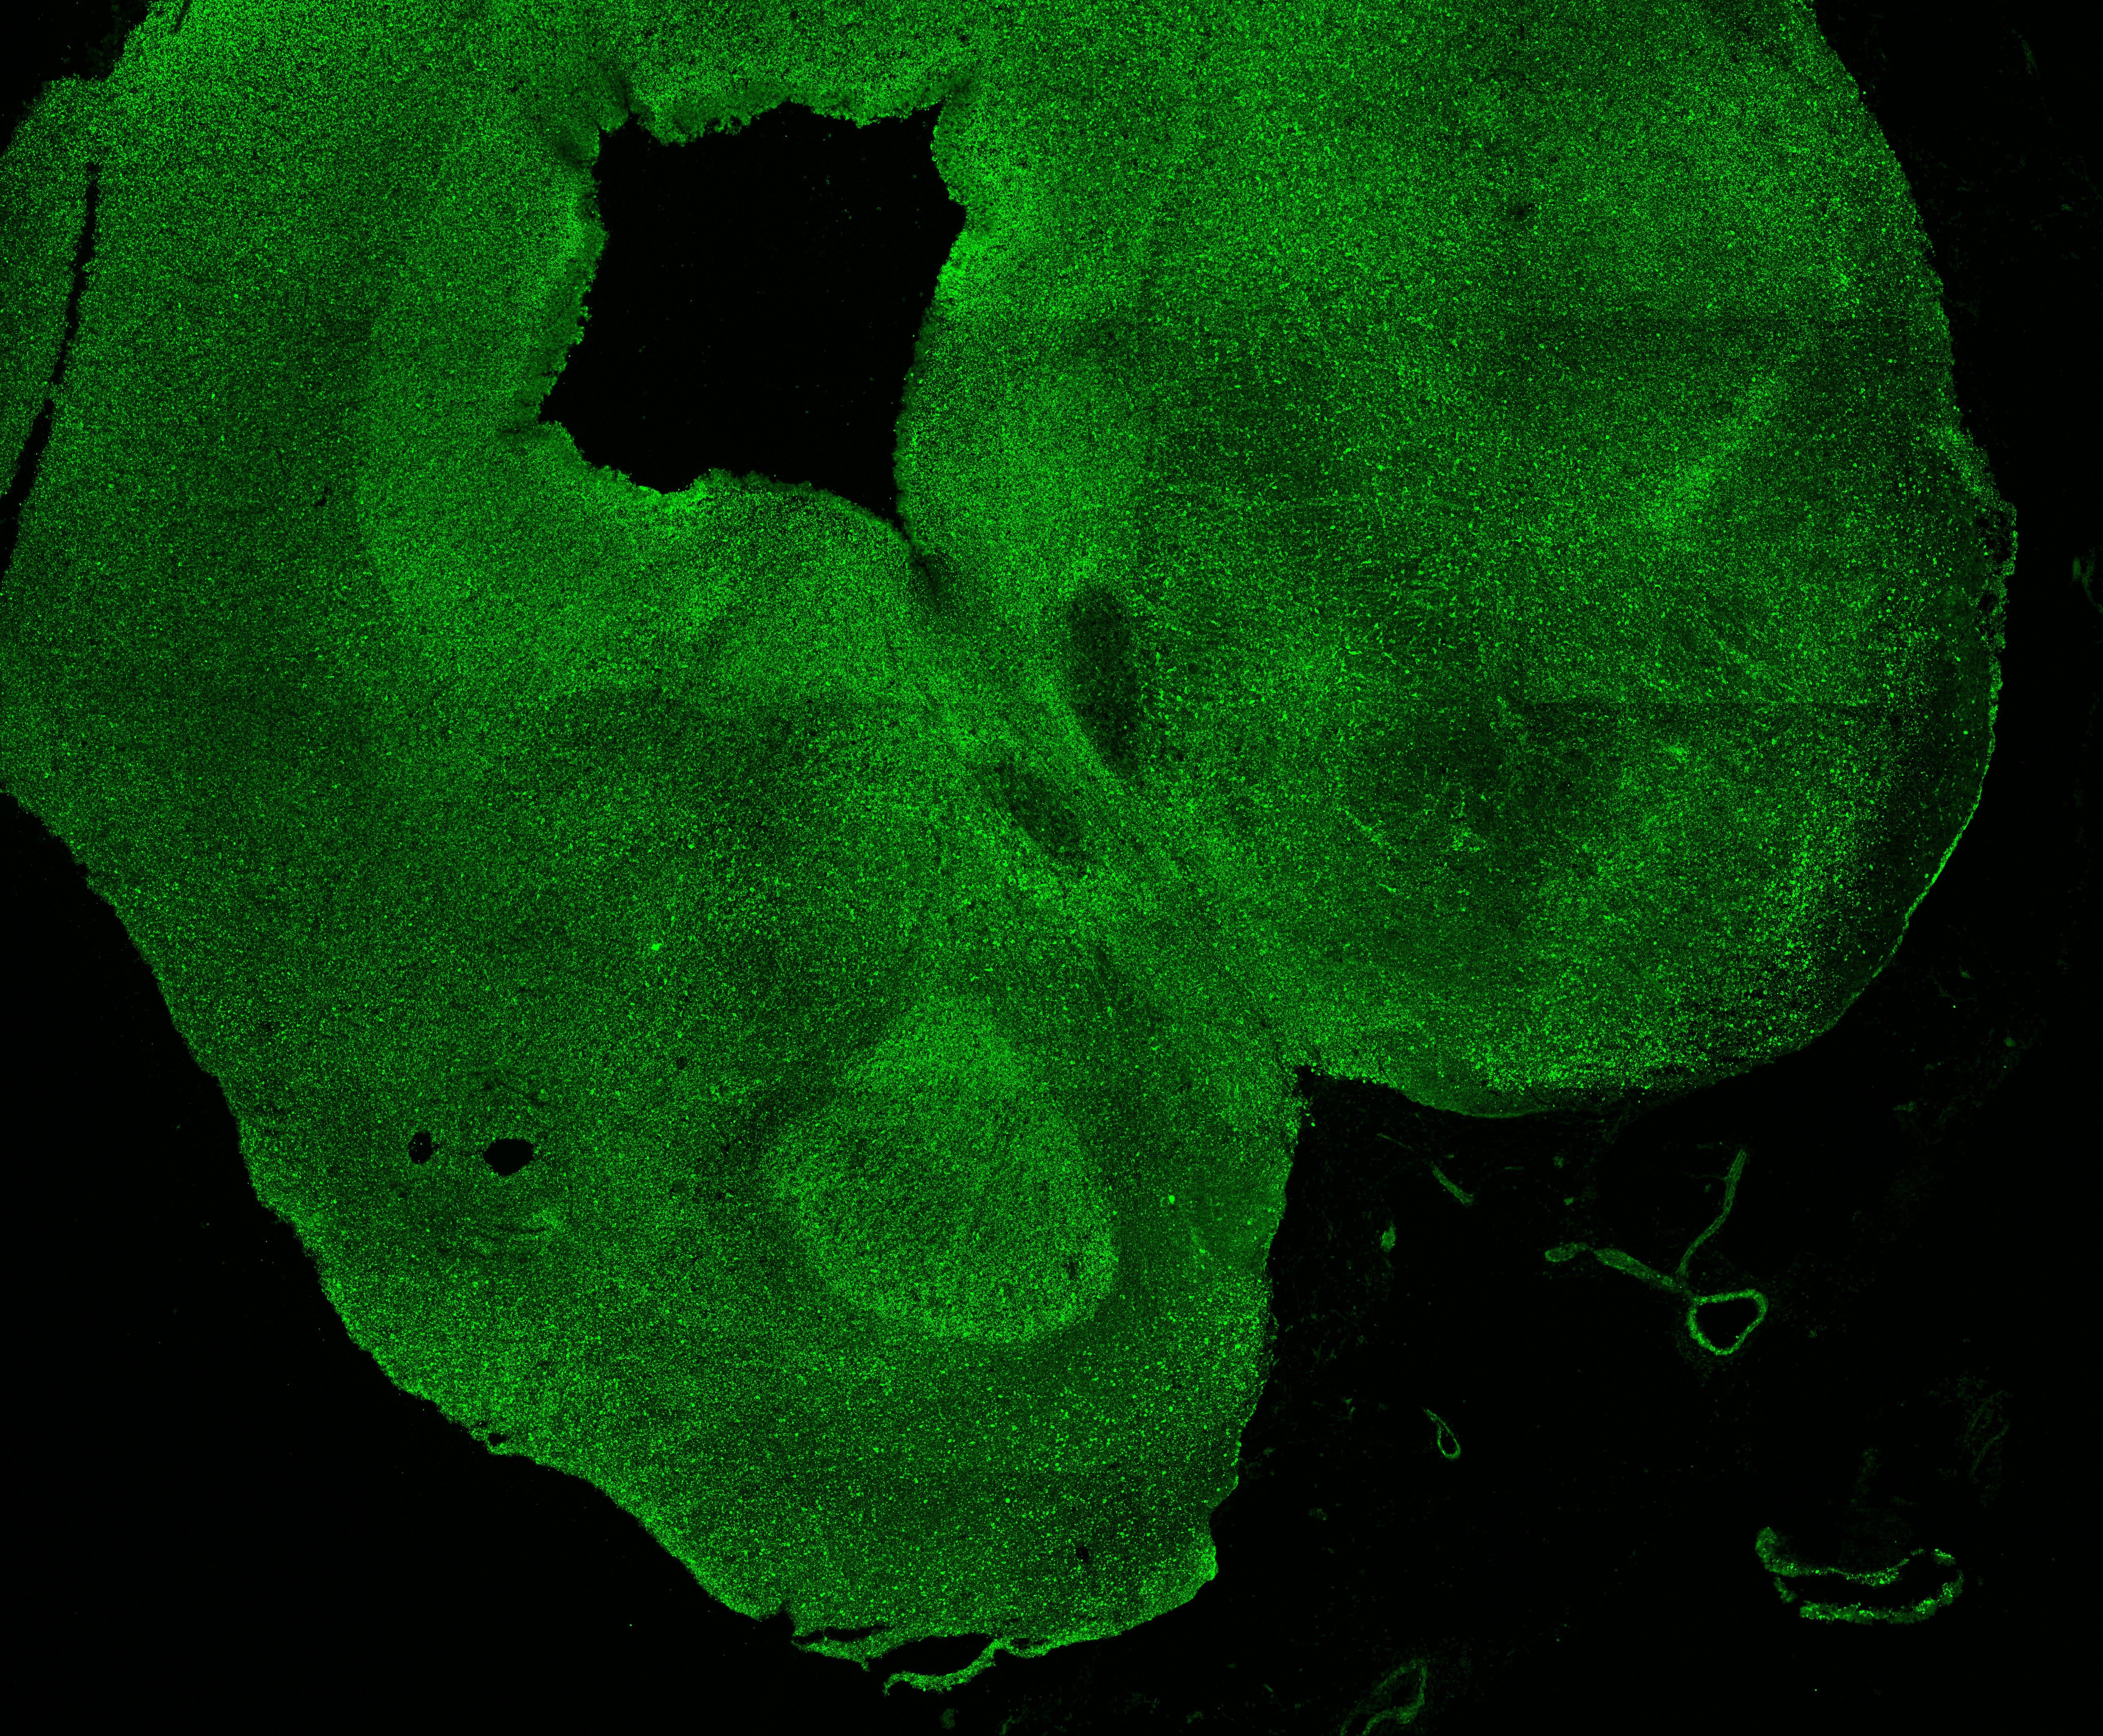

An anatomical analysis of the developing human midbrain from 6 post-conceptional weeks (PCW) to 22 PCW reveals increased tissue complexity, characterized by the emergence of dopaminergic nuclei, as highlighted by immunofluorescence analysis for tyrosine hydroxylase (TH).

11PCW

DAPI

11PCW human midbrain

MAP2

SOX2

Merged